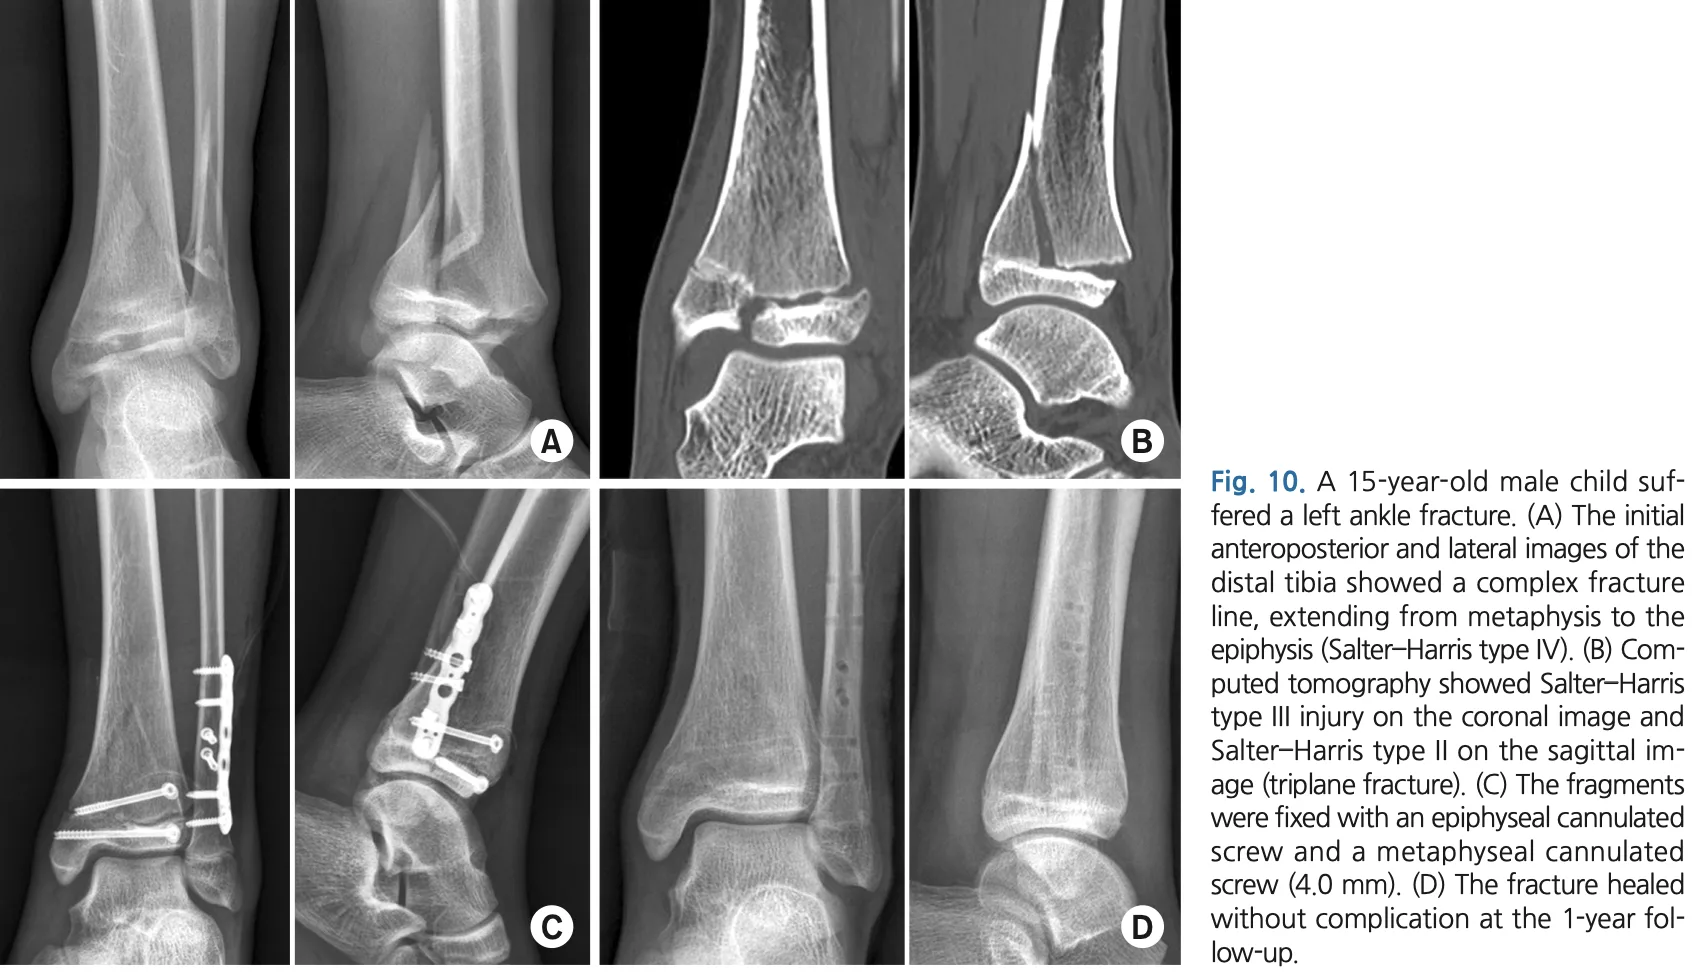

13時半から, 下腿骨遠位部骨折の高校生の手術.

後輩医師の執刀で, 私は助手を務めました.

腓骨は, 成長軟骨をまたがないように整復後にプレートとスクリューで固定.

脛骨遠位は, 整復後にスクリュー2本だけで固定しています.

引用元:Kim HY. Ankle fractures in children: Classification and treatment. J Musculoskelt Trauma. 2021. 34.

腓骨は, 遠位骨幹部で大きく転位しており, 整復した後にプレートで固定.

骨端線が残っている年齢のため, 骨端線を損傷しないよう, 骨端線より頭側のみにスクリューを入れる工夫が必要でした.